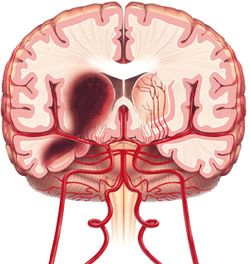

السكتات الدماغية النزفية hemorrhagic stroke

وفيها يحدث نزيف داخل الجمجمة يؤدي إلى أذية النسيج الدماغي وتشكل نحو 15 ـ 20% من الأمراض الوعائية الدماغية.

وهناك نوعان رئيسيان للنزيف الدماغي هما:

النزف الدماغي «تمزق شريان صغير داخل الدماغ يؤدي إلى خروج الدم من الوعاء إلى النسيج الدماغي».

1ـ النزيف الدماغي (أو داخل الدماغ) intracerebral hemorrhage: يؤلف نحو 10% من الأمراض الوعائية الدماغية. وفيه يحدث نزيف داخل النسيج الدماغي، مما قد يسبب خطورة كبيرة على الحياة نتيجة انضغاط المراكز الحيوية في الدماغ (كتلك المسؤولة عن التنفس).

ـ عوامل الخطورة: أهم أسباب النزيف الدماغي هو ارتفاع الضغط الشرياني. ومن الأسباب الأخرى ضعف الأوعية الدماغية لدى الكهول، كما قد يسبب استعمال المميعات الدموية ازدياد احتمال الوفاة في حال حدوث نزيف دماغي.